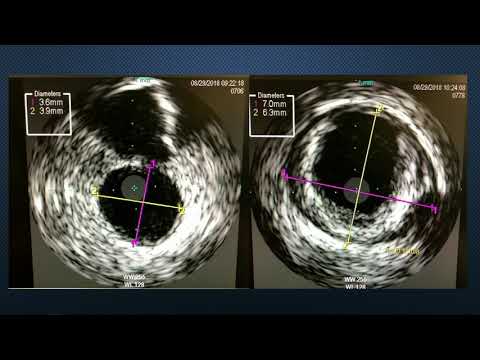

CVI2018 Session: Coronary Challenging Case Competition: Semifinals 2 (Mt. Oxford July 26, 10:30 am)

CVI2018 Coronary Challenging Case Competition: Semifinals 1 - Debraj Das, MD